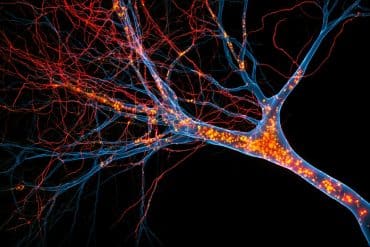

The MRIs showed that 33 percent of the people with type 1 diabetes had moderate to severe levels of white matter hyperintensities (markers of damage to the brain’s white matter, present in normal aging and neurological disorders) compared with 7 percent of their non-diabetic counterparts.

Among only the participants with type 1 diabetes, those with greater volumes of white matter hyperintensities averaged lower cognitive scores than those with smaller volumes, though the difference was less pronounced.

The study identified signs of nerve damage, such as numbness or tingling in extremities, as a risk factor for greater volumes of white matter hyperintensities.